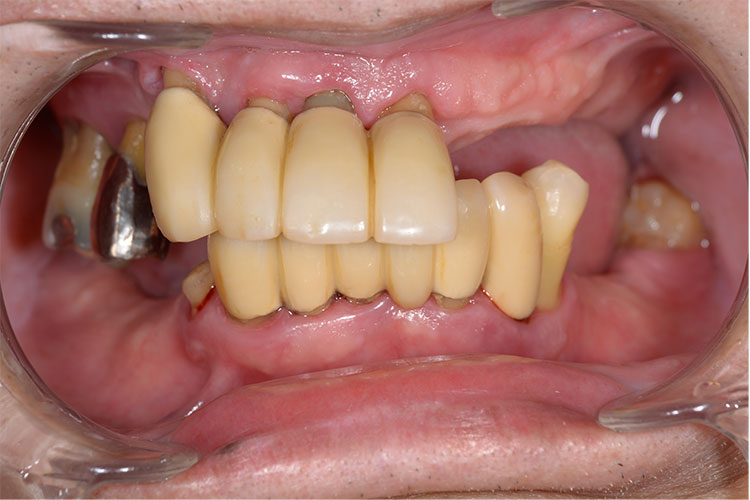

難症例のインプラント治療例【10本】

患者様

情報

治療期間

治療費

埋入数

リスクと副作用

男性

10ヶ月

5,637,600円

10本

術後に痛みや

腫れが出る恐れ